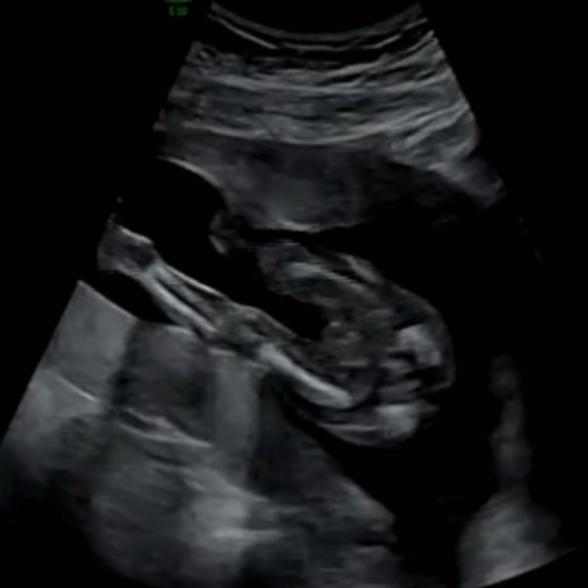

エコーの写真だけで、性別をお答えするのは、間違いがあってもよくないので、控えさせていただいております🙇